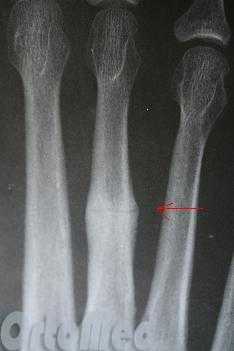

Переломы плюсневых костей

Переломы плюсневых костей по частоте занимают первое место среди всех переломов костей стопы. Обычно возникают при прямом воздействии травмирующей силы (сдавление стопы, падение тяжести или переезд стопы колесом). Могут быть множественными или одиночными. В зависимости от уровня повреждения выделяют переломы головки, шейки и тела плюсневых костей.

Одиночные переломы плюсневых костей очень редко сопровождаются значительным смещение фрагментов, поскольку оставшиеся целыми кости плюсны выполняют функцию естественной шины, удерживая отломки от смещения.

При одиночных переломах плюсневых костей выявляется локальный отек на тыле и подошве, боль при опоре и прощупывании. Множественные переломы плюсневых костей сопровождаются выраженным отеком всей стопы, кровоизлияниями, болью при пальпации. Опора затруднена или невозможна из-за боли. Возможна деформация стопы. Диагноз подтверждается данными рентгенографии в 2-х проекциях, а при переломах основания костей плюсны - в 3-х проекциях.